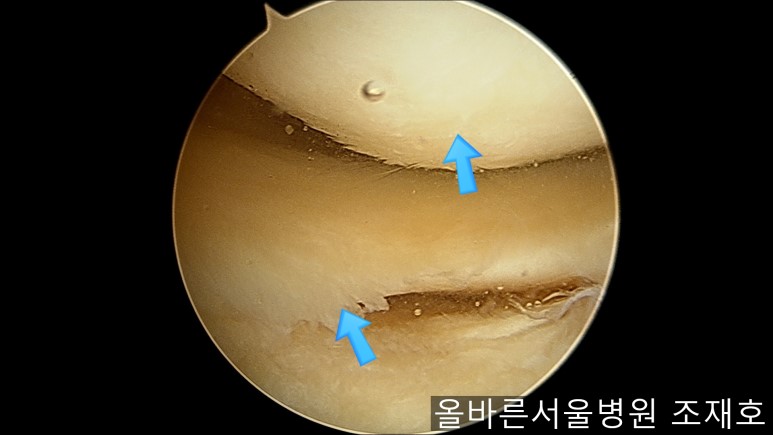

前方十字韧带处没有覆盖滑膜的粘液样变性的外观及稳定性无异常。

与内侧对照,外侧的软骨及软骨板无损伤。